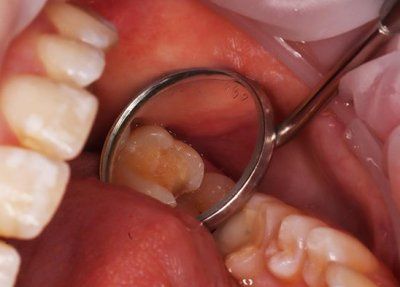

Клинический случай: зуб 26, средний кариес. На зубе 26 на жевательной, медиальной поверхности дефект твердых тканей.

Реставрация – OptiBond Solo Plus, материал - Filtek Z-250 A2.